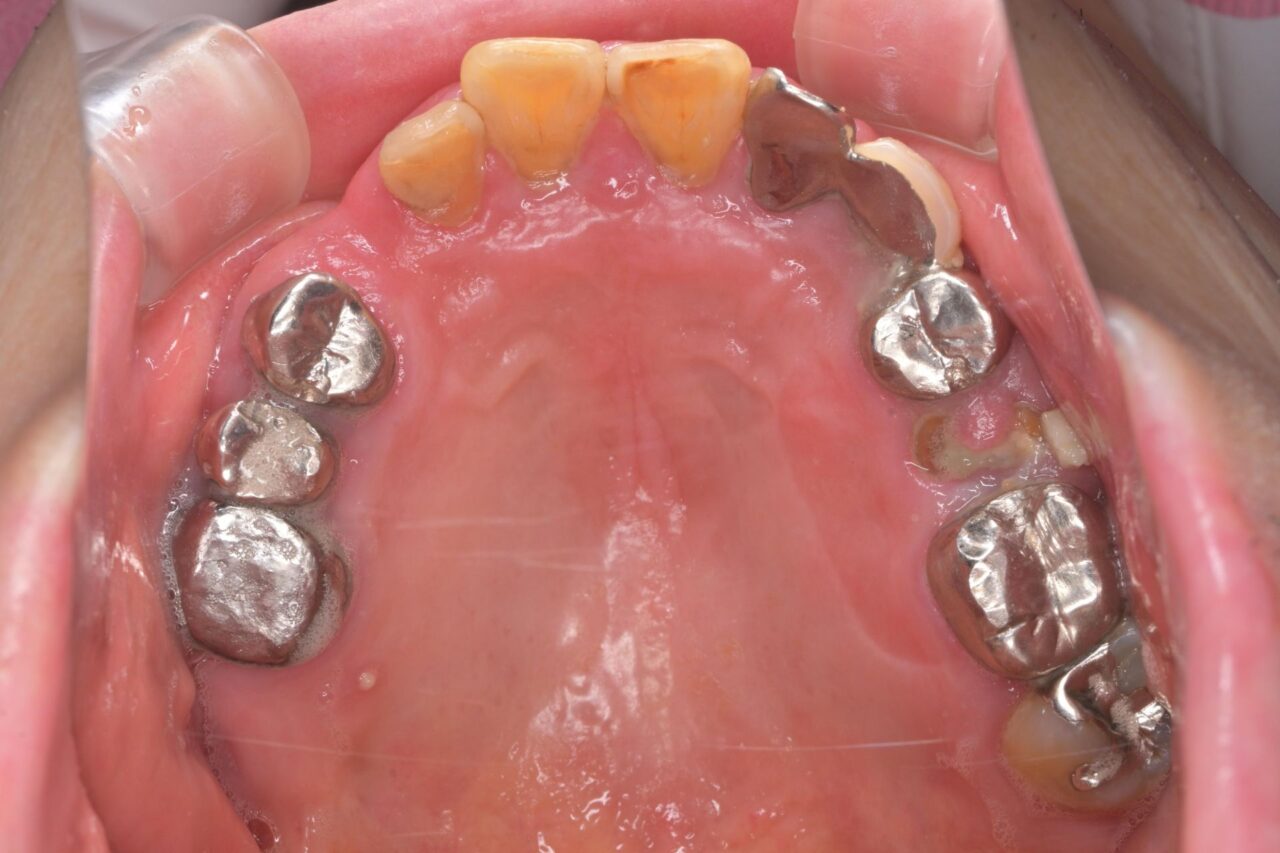

上面

虫歯を放置して残根状態です。このような歯を放置すると命の危険にさらされます。

下面

親知らずが残っていますね。

びわ湖大津デンタルクリニックでは、不要な親知らずは即抜歯です。

ブリッジも不衛生かつ虫歯になっていますので、迷わず撤去。